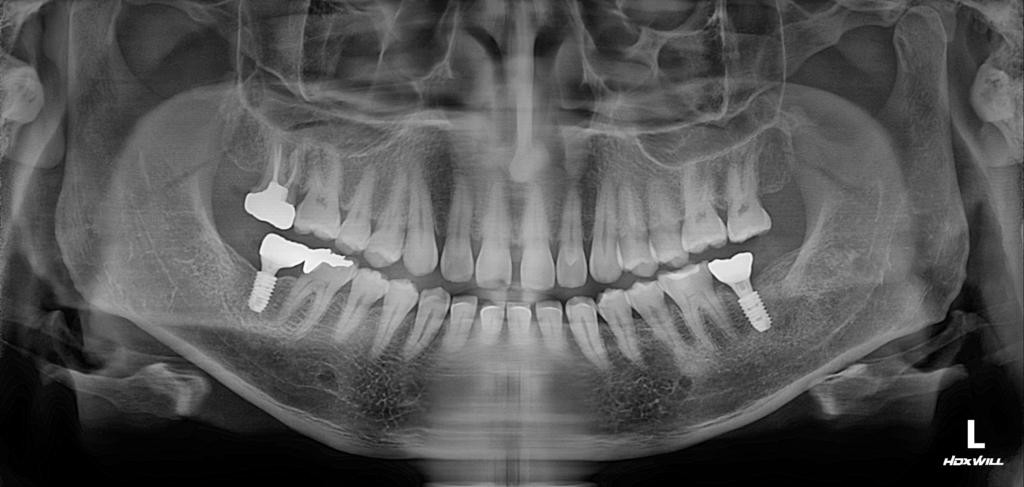

내원 당시 촬영한 사진을 보면 오른쪽 아래, 즉 #37 부위에 식립된 임플란트에 문제가 발생한 상태임을 확인할 수 있었습니다.

사진상 왼쪽 아래 임플란트 역시 이상적인 상태라고 보기는 어렵지만, 특히 오른쪽 하악 부위 임플란트는 뿌리 주변으로 염증이 상당히 진행된 모습이 뚜렷하게 관찰되었습니다.

방사선 사진을 살펴보면 임플란트 주위가 음영으로 보이며, 지지해야 할 뼈가 소실되면서 임플란트 상단이 이미 골 상방으로 많이 노출된 상태임을 알 수 있습니다. 게다가 환자분께서 저작 시 불편감까지 호소하고 계셨기 때문에, 기존 보철물의 형태 역시 함께 점검하고 조정할 필요가 있는 상황이었습니다.